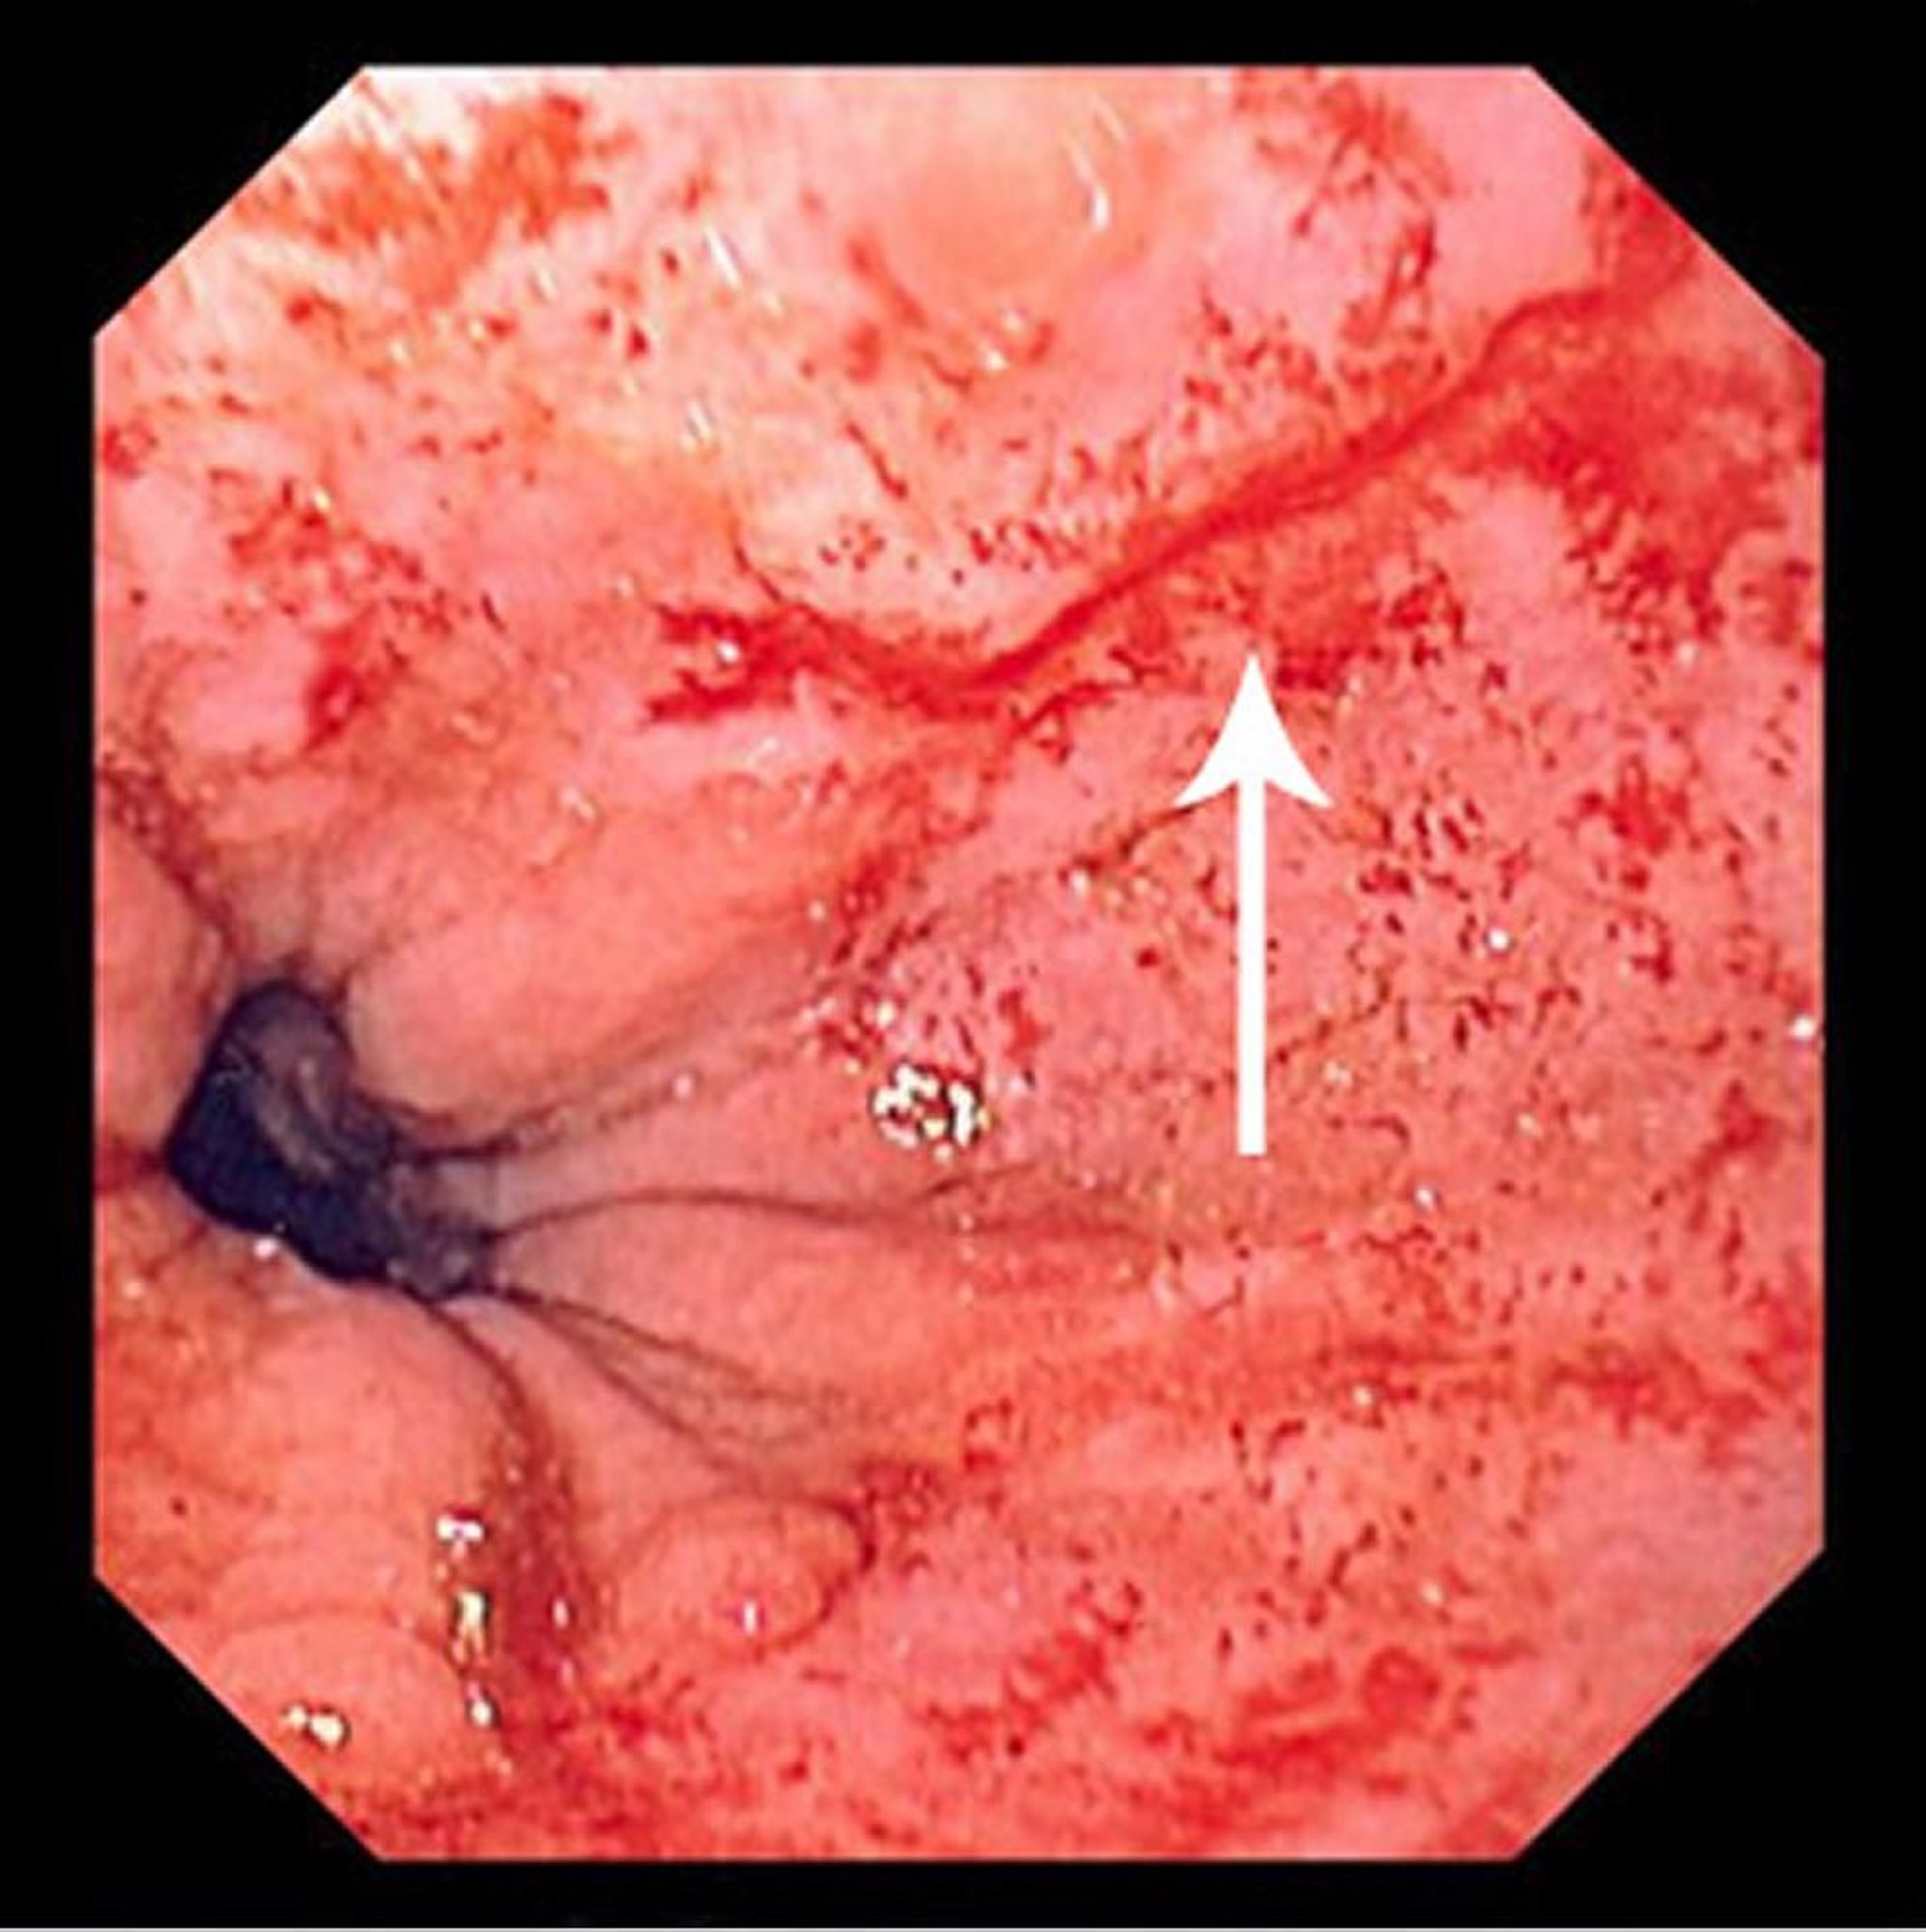

Déchirure de Mallory-Weiss

Cette photographie montre une fine déchirure de Mallory-Weiss (flèche).

Image fournie par le Dr David M. Martin.